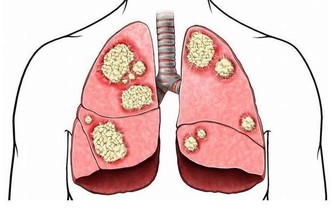

6、喝酒、抽煙

幾乎所有癌症的誘因裡都有它們的身影。有研究認為,吸煙可以對肺、大腸產生長期性、持續性的慢性刺激,從而誘發肺癌、大腸癌。